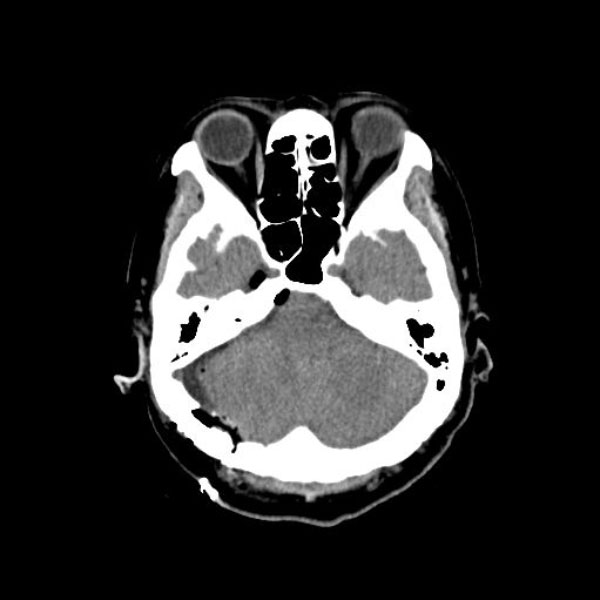

症例 '26年4月

No.

590

当院外来

'26年4月

60代

三叉神経痛第3枝領域

(顔面の痛みをとること)

手術前

減圧前

減圧後

術後血管撮影